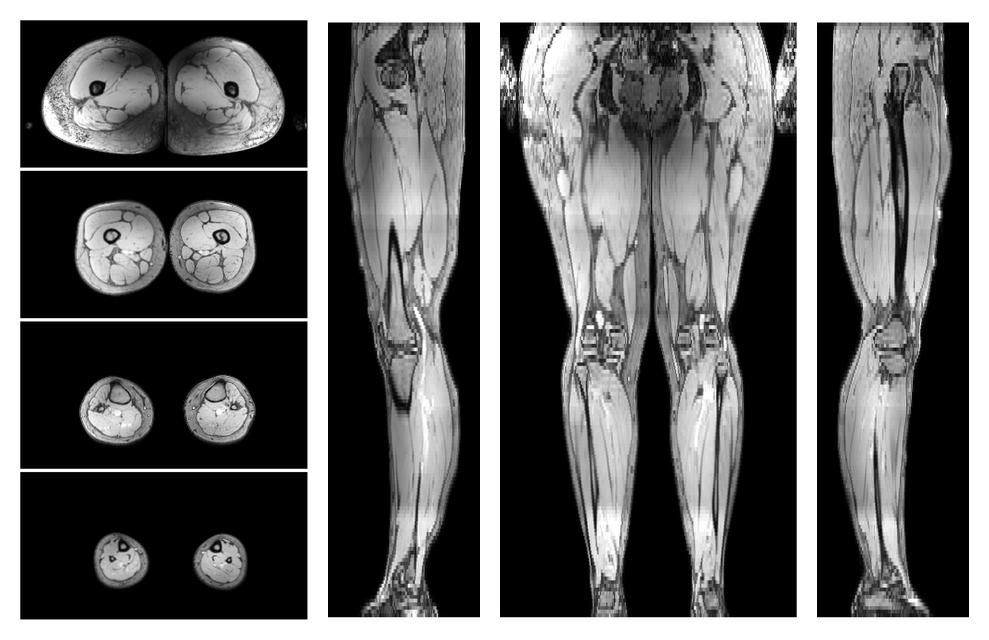

Water only T2 mapping

Multi echo spin echo T2 relaxation time mapping with EPG reconstruction, for information look here».

• Water only signal

The water part of the acquired multi-echo spin echo data.

• Water only T2 relaxation time

The water only T2 relaxation time of the lower extremity obtained from multi echo spin echo t2 mapping with EPG based reconstruction.